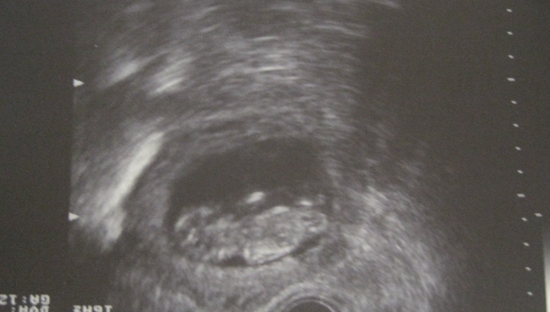

ВОТ МЫ КАКИЕ.....малюсенькие !!

Всего 52 мм..мой малышок!! как же я тебя люблю!!!!